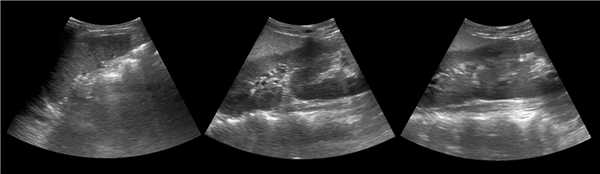

Клинический пример из первой группы. Пациент М., с хронической почечной недостаточностью. Трансплантация почки произведена от живого родственного донора. Трансплантат находится в правой подвздошной области. При нормальном функциональном состоянии трансплантата, показатели цветовой и спектральной допплерографии оценивались как удовлетворительные, с индексом резистентности не более 0,60 (рис. 1); показатели жесткости паренхимы почечного трансплантата при УЭСВ на различных участках составили от 20,05 до 29,18 кПа (рис. 2-4).

Рисунок 2. Исследование в режиме ультразвуковой эластографии сдвиговой волны у пациента М.: жесткость паренхимы в зоне медиального края трансплантата 19,8 кПа

Рисунок 3. Исследование в режиме ультразвуковой эластографии сдвиговой волны у пациента М.: жесткость паренхимы в зоне верхнего полюса почечного трансплантата 21,4 кПа

Рисунок 4. Исследование в режиме ультразвуковой эластографии сдвиговой волны у пациента М.: жесткость паренхимы в зоне нижнего полюса почечного трансплантата 16,8 кПа